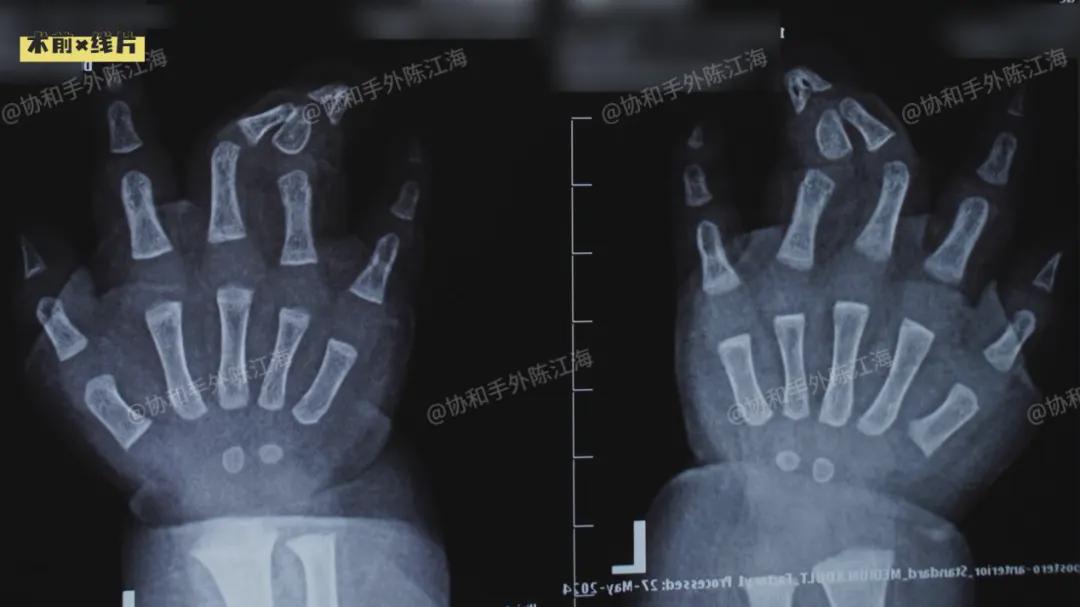

这是一个双手双脚都存在着并指的孩子。双脚情况相似,第4、5趾粘黏在一起,还有多趾。

双手情况则更为复杂:右手是单纯的并指,而左手不仅并指,还有多指的存在。

我们查看了孩子的情况,双脚是我们比较常见的多并趾,右手的并指相对好处理,左手会相对复杂。